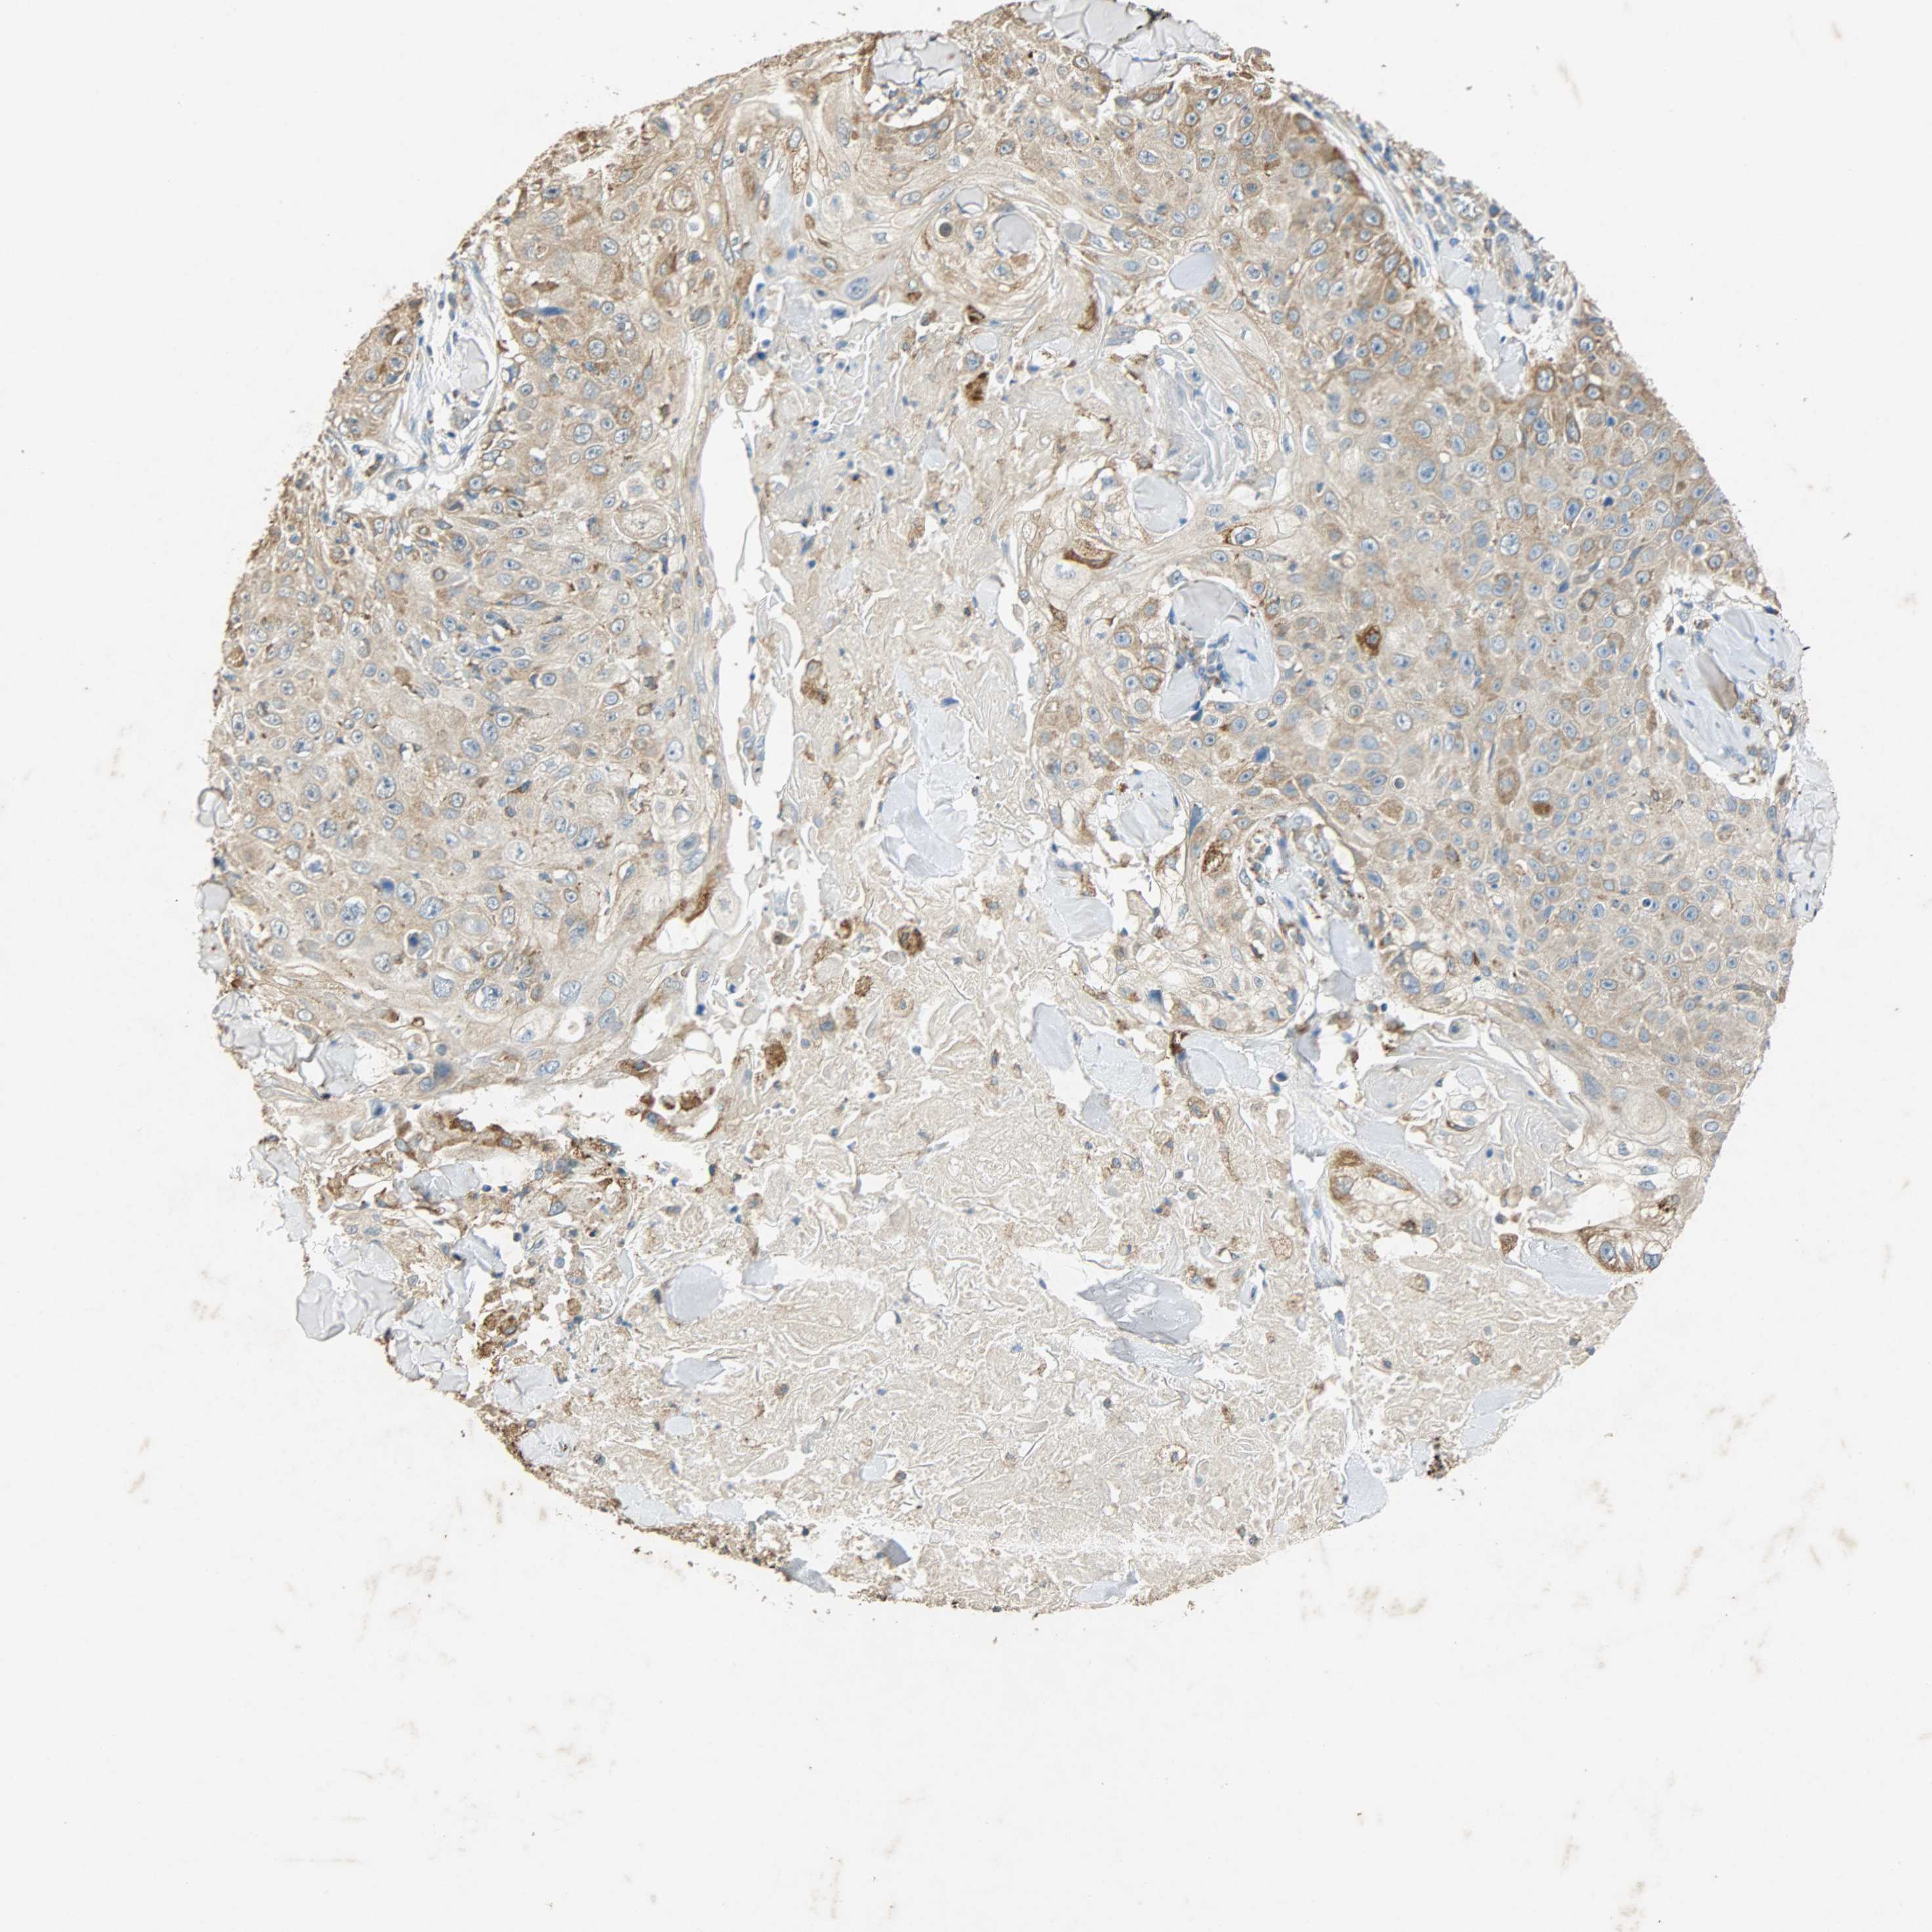

SKIN CANCER - Protein expressioni

A mouse-over function shows sample information and annotation data. Click on an image to view it in a full screen mode. Samples can be filtered based on level of antibody staining by selecting one or several of the following categories: high, medium, low and not detected. The assay and annotation is described here.

Each image is clickable and will lead to virtual microscopy that enables deeper exploration of all samples and also displays staining intensity scores, fraction scores and subcellular localization as well as patient and tissue information for each sample.

Antibody HPA038845

Antibody CAB005221

Staining

High

Medium

Low

Not detected

Intensity

Strong

Moderate

Weak

Negative

Quantity

>75%

75%-25%

<25%

None

Location

Nuclear

Cytoplasmic/membranous

Cytoplasmic/membranous,nuclear

Basal cell carcinoma

Squamous cell carcinoma, NOS

Squamous cell carcinoma, metastatic, NOS